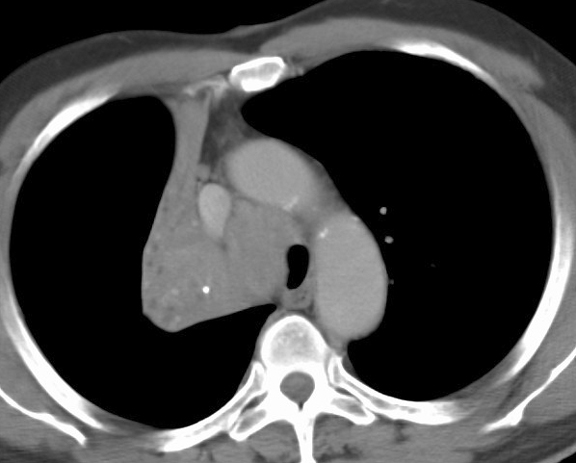

Gallery Lobar Collapse RUL Collapse RUL Collapse Case 1 CT(a)

RUL Collapse Case 1 CT(a)